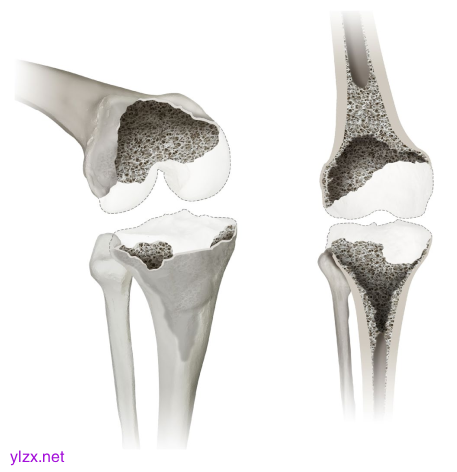

显示膝关节缺陷分类(KDC)的2型缺陷。在2型缺陷中,外科医生会遇到干骺端松质骨耗竭和/或干骺皮质骨(小于周长的50%)的固有缺陷,这在3D斜视图(左)和正视图(右)中显示